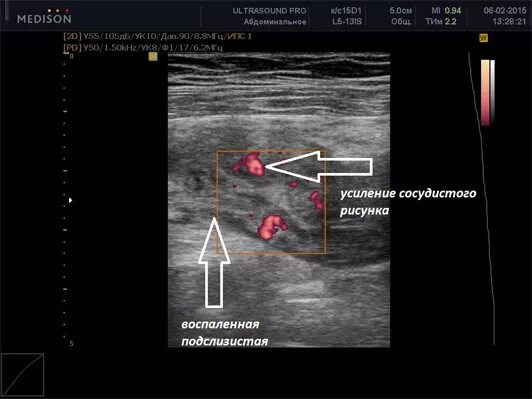

Узи прямой кишки как делают